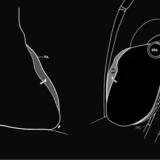

Left chambers Lat

Date: 03/02/2006

Views: 2358